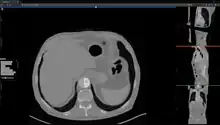

Studierfenster or StudierFenster (SF)[1][2][3] is a free, non-commercial open science client/server-based medical imaging processing online framework. It offers capabilities, like viewing medical data (computed tomography (CT), magnetic resonance imaging (MRI), etc.) in two- and three-dimensional space directly in standard web browsers, like Google Chrome, Mozilla Firefox, Safari, and Microsoft Edge. Other functionalities are the calculation of medical metrics (dice score[4] and Hausdorff distance[5]), manual slice-by-slice outlining of structures in medical images (segmentation[6][7]), manual placing of (anatomical) landmarks in medical image data, viewing medical data in virtual reality, a facial reconstruction and registration of medical data for augmented reality,[8] one click showcases for COVID-19 and veterinary scans, and a Radiomics module.